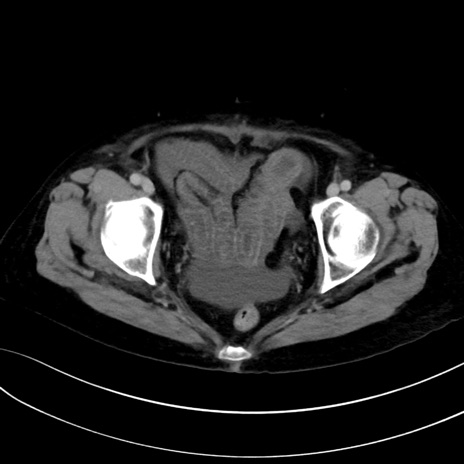

症例13 CT(横断像)1日半後